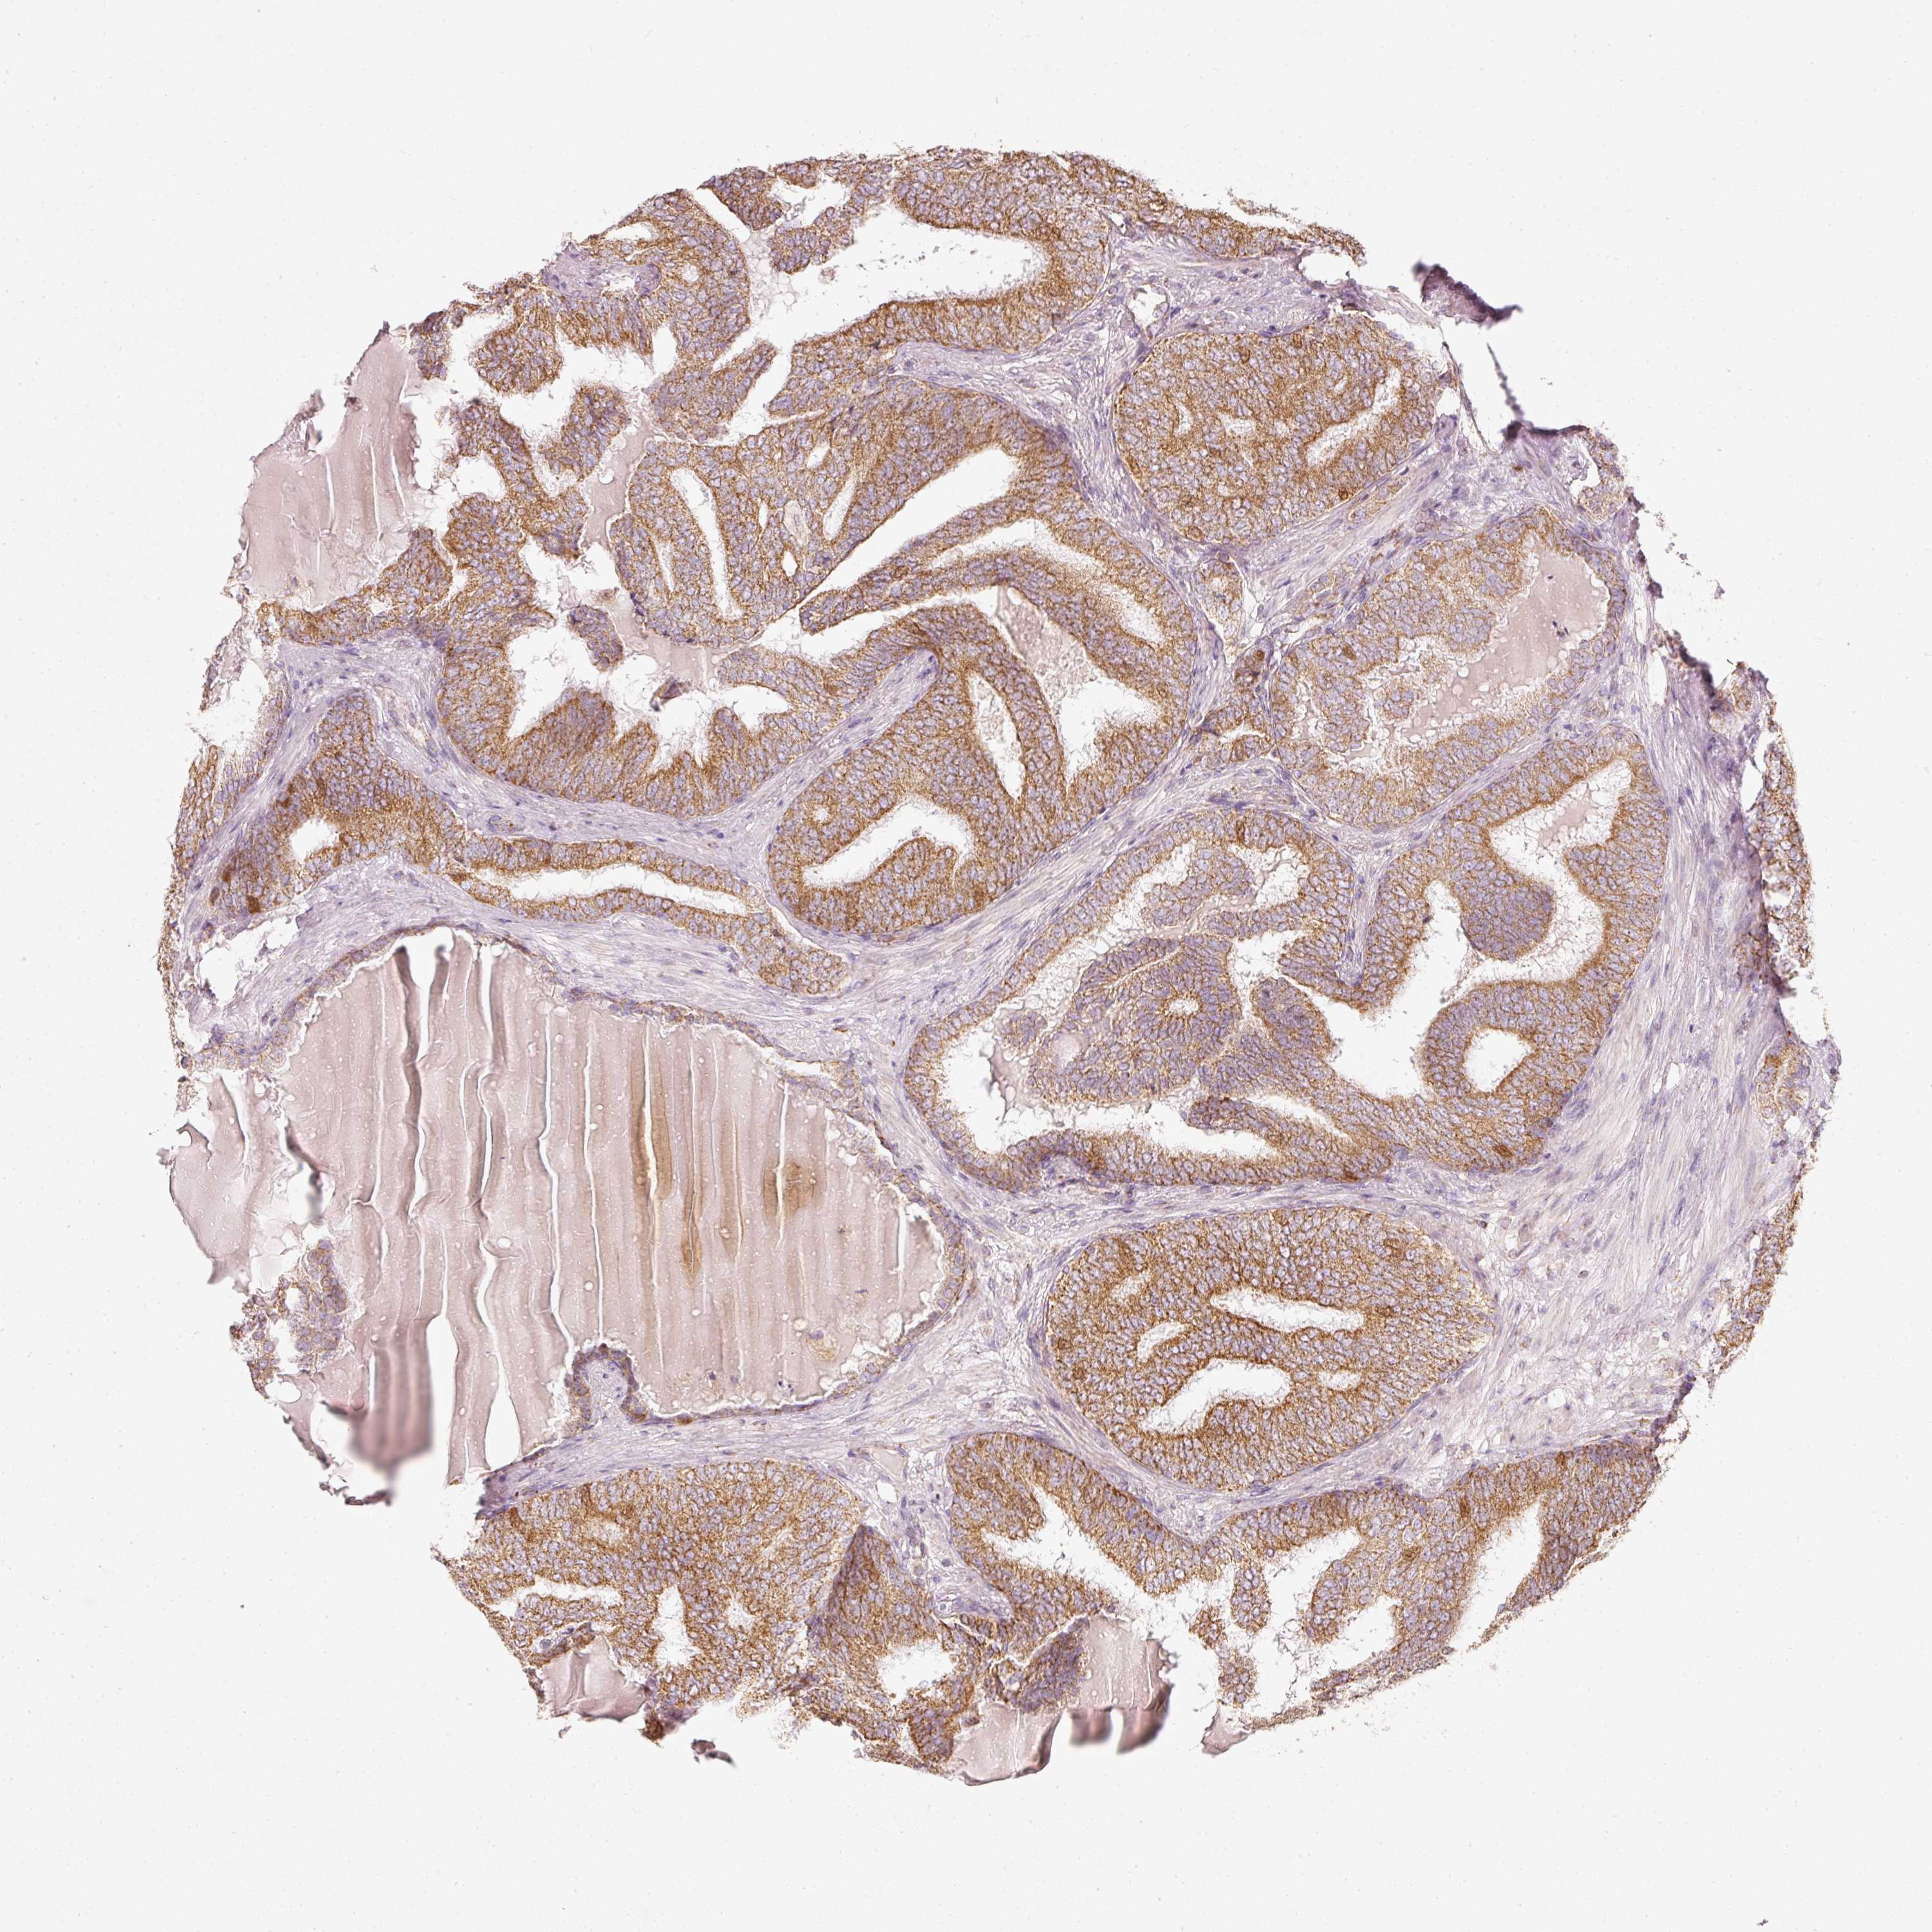

PROSTATE CANCER - Protein expressioni

A mouse-over function shows sample information and annotation data. Click on an image to view it in a full screen mode. Samples can be filtered based on level of antibody staining by selecting one or several of the following categories: high, medium, low and not detected. The assay and annotation is described here.

Note that samples used for immunohistochemistry by the Human Protein Atlas do not correspond to samples in the TCGA dataset.

Antibody stainingi

Antibody staining in the annotated cell types in the current human tissue is reported as not detected, low, medium, or high, based on conventional immunohistochemistry profiling in selected tissues. This score is based on the combination of the staining intensity and fraction of stained cells.

Each image is clickable and will lead to virtual microscopy that enables deeper exploration of all samples and also displays staining intensity scores, fraction scores and subcellular localization as well as patient and tissue information for each sample.

Antibody HPA054422

Antibody HPA060360

Staining

High

Medium

Low

Not detected

Intensity

Strong

Moderate

Weak

Negative

Quantity

>75%

75%-25%

<25%

None

Location

Nuclear

Cytoplasmic/membranous

Cytoplasmic/membranous,nuclear

Adenocarcinoma, High grade

Adenocarcinoma, Low grade